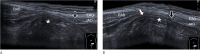

Inguinal hernia is the most prevalent type of abdominal wall hernia. Indirect inguinal hernia is twice as common as direct inguinal hernia. Computed tomography and magnetic resonance imaging can be used to evaluate inguinal hernia, but these modalities are greatly limited by their cost and availability. Ultrasonography has emerged as the most convenient imaging tool for diagnosing inguinal hernia due to its advantages, such as portability and absence of radiation. The present pictorial review presents an overview on the use of ultrasonography in the evaluation of inguinal hernia with a particular emphasis on the regional anatomy, relevant scanning tips, identification of subtypes, postoperative follow-up, and diagnosis of pathologies mimicking inguinal hernia.